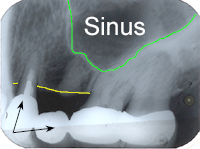

Bei einer 59 Jahre alten Frau muss wegen Wurzelbruchs und Vereiterung des ersten Brückenpfeilers (1. Zahn im Röntgenbild von Abb. 1 links) ein Zahn gezogen und das folgende Zwischenglied der Brücke rechts davon (schwarze Pfeile in Abb. 1) entfernt werden. Es entsteht im Oberkiefer links eine unschöne, ästhetisch sehr empfindliche Lücke von 14 mm.

In Abb. 2 sieht man, wie wir einen Sinuslift gemacht haben, um zwei Implantate setzen zu können. Dabei verwendeten wir ein Transplantationsgemisch mit 10% Eigenknochen und 90% Substitut. Der ortsständige Knochen beträgt beim ersten Implantat 12 mm (nur die Implantatspitze hätte in den ehemaligen Sinus geragt), beim zweiten Implantat 6 mm.

| Verlauf des Kieferhöhlenbodens vor Sinuslift | |

| Verlauf des Kieferkammes | |

| Gebiet zwischen gelber und grüner Linie: ortsständige Knochenhöhe | |

| Neuer Verlauf des Kieferhöhlenbodens | |

| Gebiet zwischen roter und grüner Linie: Knochenaufbau, Sinuslift | |

In Abb. 3 sind die zementierten Implantatkronen sieben Monate nach dem Sinuslift im Röntgenbild zu sehen. Die eigenen, bestehenden Kronen hinter den neuen Implantatkronen konnten somit gerettet werden. Abb. 4 zeigt das klinische, intraorale Resultat zwei Jahre nach der Behandlung und Abb. 5 das "happy smiling" der extraoralen Situation nach der Behandlung.